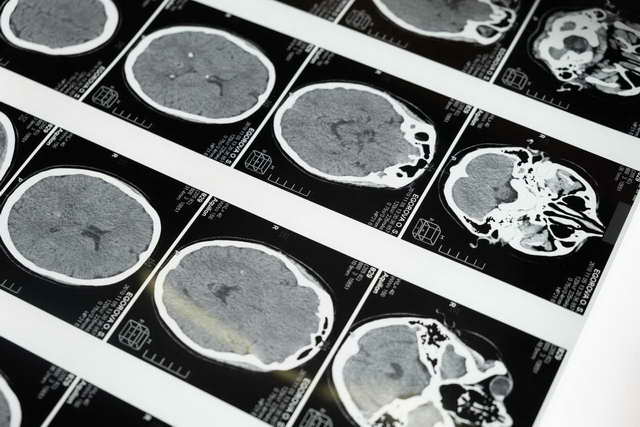

Over the next few hours, her local hospital performed a CT scan and administered the prescribed cocktail of medications. When the scans came back clear, the doctor thought she should still have an MRI the next day, so they admitted her overnight. Initially, her symptoms seemed to be resolving, but in the morning things had become worse. Katie recalls, “When I woke up the next morning, [these symptoms] got severely worse. I lost everything on my left side and I couldn’t talk, pretty much, at all.” Stumped, the decision was made to send her to a different hospital in London, Ontario which was larger and had a neurologist on staff. It was felt that with London’s additional resources and specialists, an answer might be found.